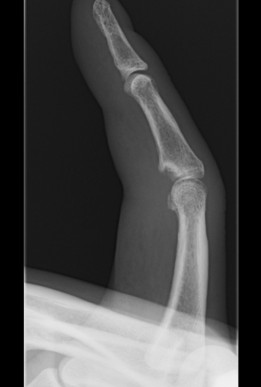

Suzuki / Slade Dynamic Distraction external fixator

Concept

- closed reduction through ligamentotaxis

- early motion of PIPJ

Technique

- transverse K wire in rotational centre / head P1

- transverse K wire distal P2

- attached by rubber bands

- third K wire mid-diaphysis P2, prevents dorsal translation of MP